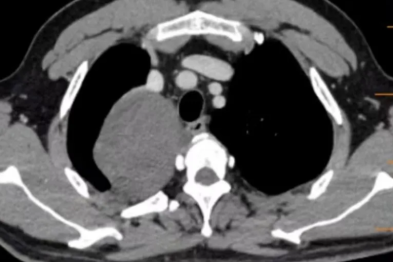

9 cm 胸腔巨瘤「盘踞」体内,微创技术如何巧妙化解危机?